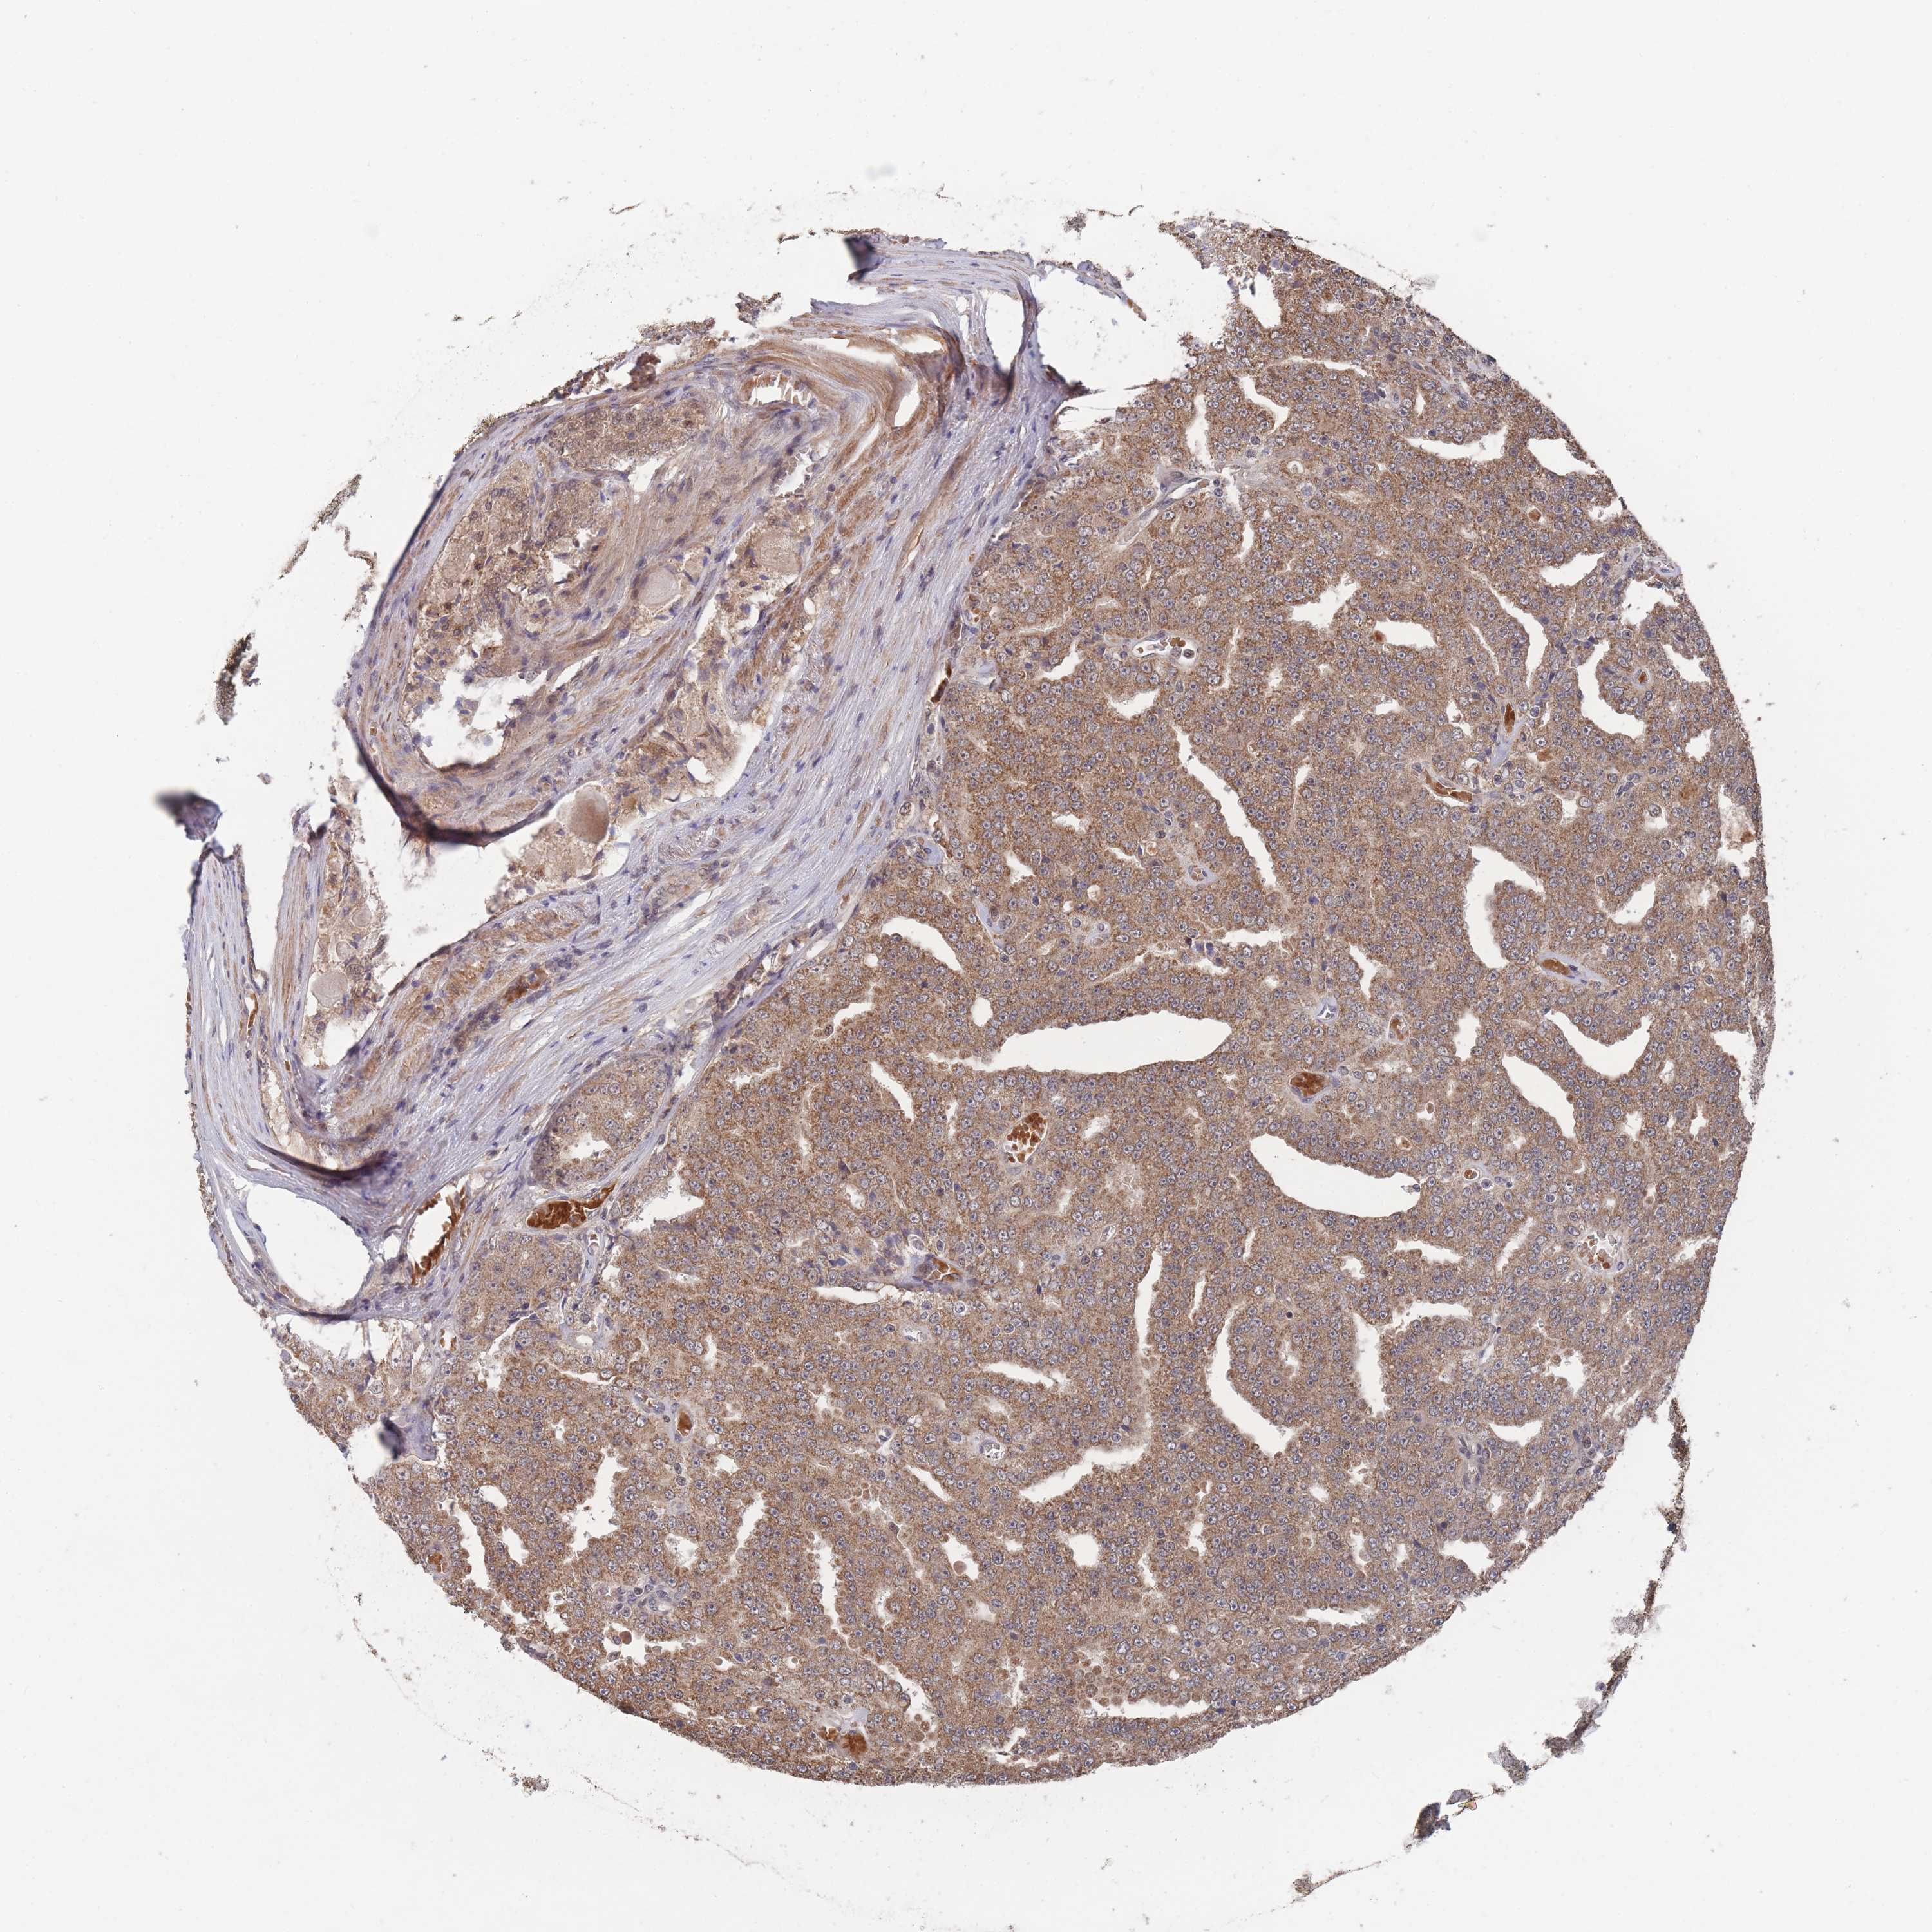

PROSTATE CANCER - Protein expressioni

A mouse-over function shows sample information and annotation data. Click on an image to view it in a full screen mode. Samples can be filtered based on level of antibody staining by selecting one or several of the following categories: high, medium, low and not detected. The assay and annotation is described here.

Note that samples used for immunohistochemistry by the Human Protein Atlas do not correspond to samples in the TCGA dataset.

Antibody stainingi

Antibody staining in the annotated cell types in the current human tissue is reported as not detected, low, medium, or high, based on conventional immunohistochemistry profiling in selected tissues. This score is based on the combination of the staining intensity and fraction of stained cells.

Each image is clickable and will lead to virtual microscopy that enables deeper exploration of all samples and also displays staining intensity scores, fraction scores and subcellular localization as well as patient and tissue information for each sample.

Antibody HPA050275

Staining

High

Medium

Low

Not detected

Intensity

Strong

Moderate

Weak

Negative

Quantity

>75%

75%-25%

<25%

None

Location

Nuclear

Cytoplasmic/membranous

Cytoplasmic/membranous,nuclear

Adenocarcinoma, High grade

Adenocarcinoma, Low grade